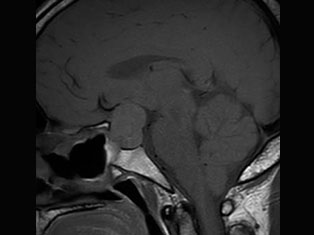

Brain Tumors

A brain tumor is a mass or growth of abnormal cells in your brain. Many different types of brain tumors exist. Some brain tumors are noncancerous (benign), and some brain tumors are cancerous (malignant).